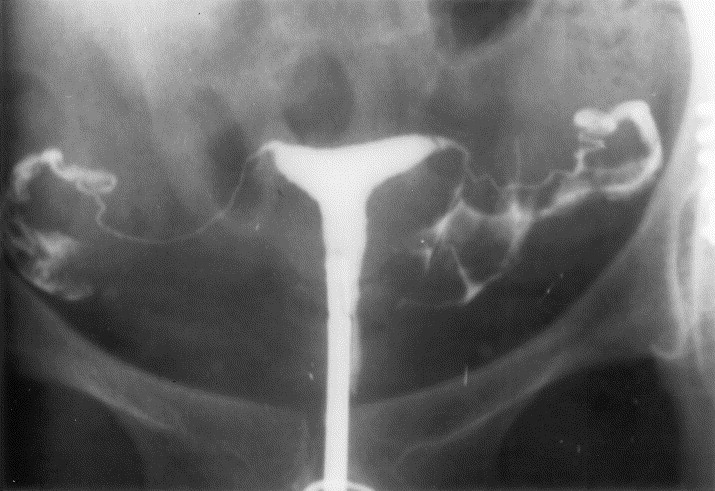

HSG is a special X-ray examination which looks at the inside of your womb (uterus) and fallopian tubes. It aims to show whether your uterus is normal and if your fallopian tubes are blocked or not.

A speculum will be inserted into your vagina and a small catheter will be passed through the cervix into the neck of the womb. A small amount of fluid will be pushed into your womb. The fluid will fill your womb and pass through your fallopian tubes. As this happens X-rays will be taken that will show the fluid within the womb and tubes.